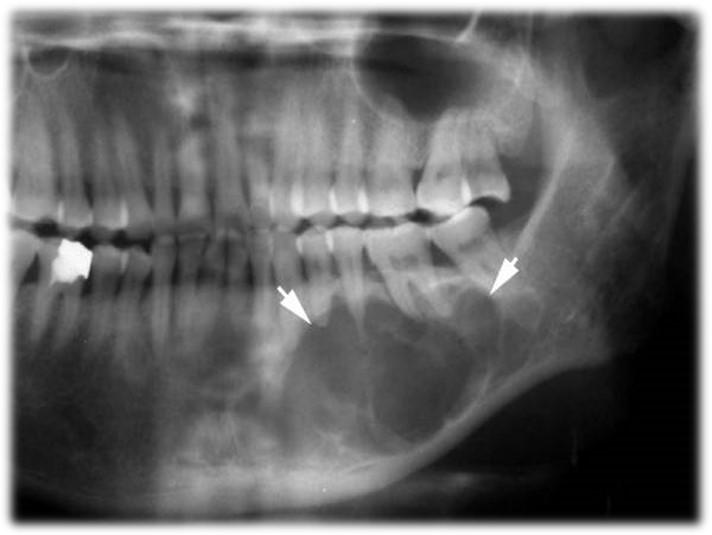

一、成釉细胞纤维瘤

一种较少见的牙源性肿瘤,其主要特征是牙源性上皮和间叶组织同时增殖,但不伴牙本质和牙釉质形成,因此它是一种真性混合性牙源性肿瘤。

1)临床表现

临床多见于儿童和青年人,平均年龄为15岁;男女性别无明显差异,最常的部位是下颌磨牙区,肿瘤生长缓慢,除颌骨膨大外,无明显症状。

X线表现为界限清楚的放射透光区(图14.2-1),与成釉细胞瘤不易区别。

图14.2-1 成釉细胞纤维瘤(X线)